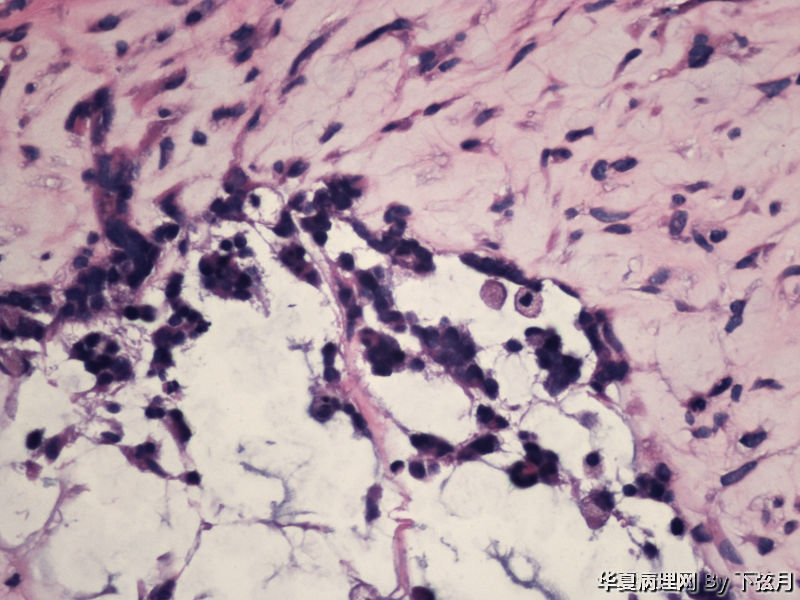

描述:HE 400倍

描述:HE 400-2

This enhancing lesion with GFAP positive cells and should consider some type of glioma, probably high-grade.

But some cells in fig 7 and 8 are worrisome, need to rule out other type tumors, like chordoma. Other small round blue cell tumors.

考虑黏液型乳头状室管膜瘤

丰富黏液背景,漂浮乳头状或簇状分布的瘤细胞,免疫组化GFAP,S-100阳性。

有血管轴乳头,粘液样物中漂浮的细胞呈团块状和小乳头状。支持粘液型乳头状室管膜瘤。